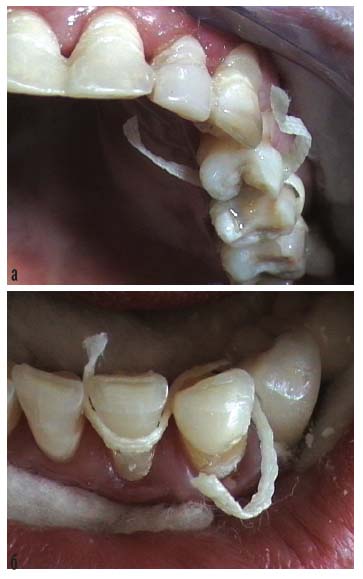

Составлен план ортопедического лечения. Шинирование подвижных зубов проведено АШ с использованием в качестве армирующего компонента ленты «Ribbond». Дефекты нижнего зубного ряда восстановлены металлокерамическими мостовидными протезами, опорные коронки которых изготовлены с апроксимальными петлями для объединения с соседними зубами в моноблок с помощью шинирующей ленты (рис. 11 – 15).

Рис. 11. Клиническая картина до протезирования

Рис. 12. Металлокерамический мостовидный протез, опорные коронки которого имеют апроксимальные петли для заведения эластичной шинирующей ленты – а; ортопантомограмма после протезирования нижнего зубного ряда – б